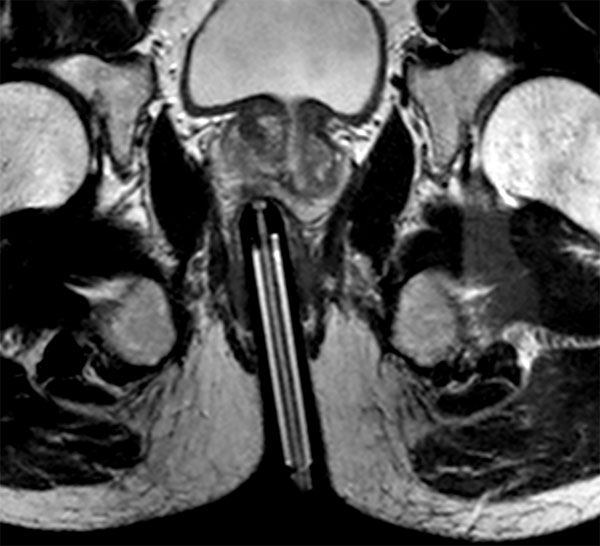

73 year old male with known prostate carcinoma. Size of 5mm, located in right posterior region. Patient is under active surveillance. Request for MR-guided prostate biopsy to re-evaluate.